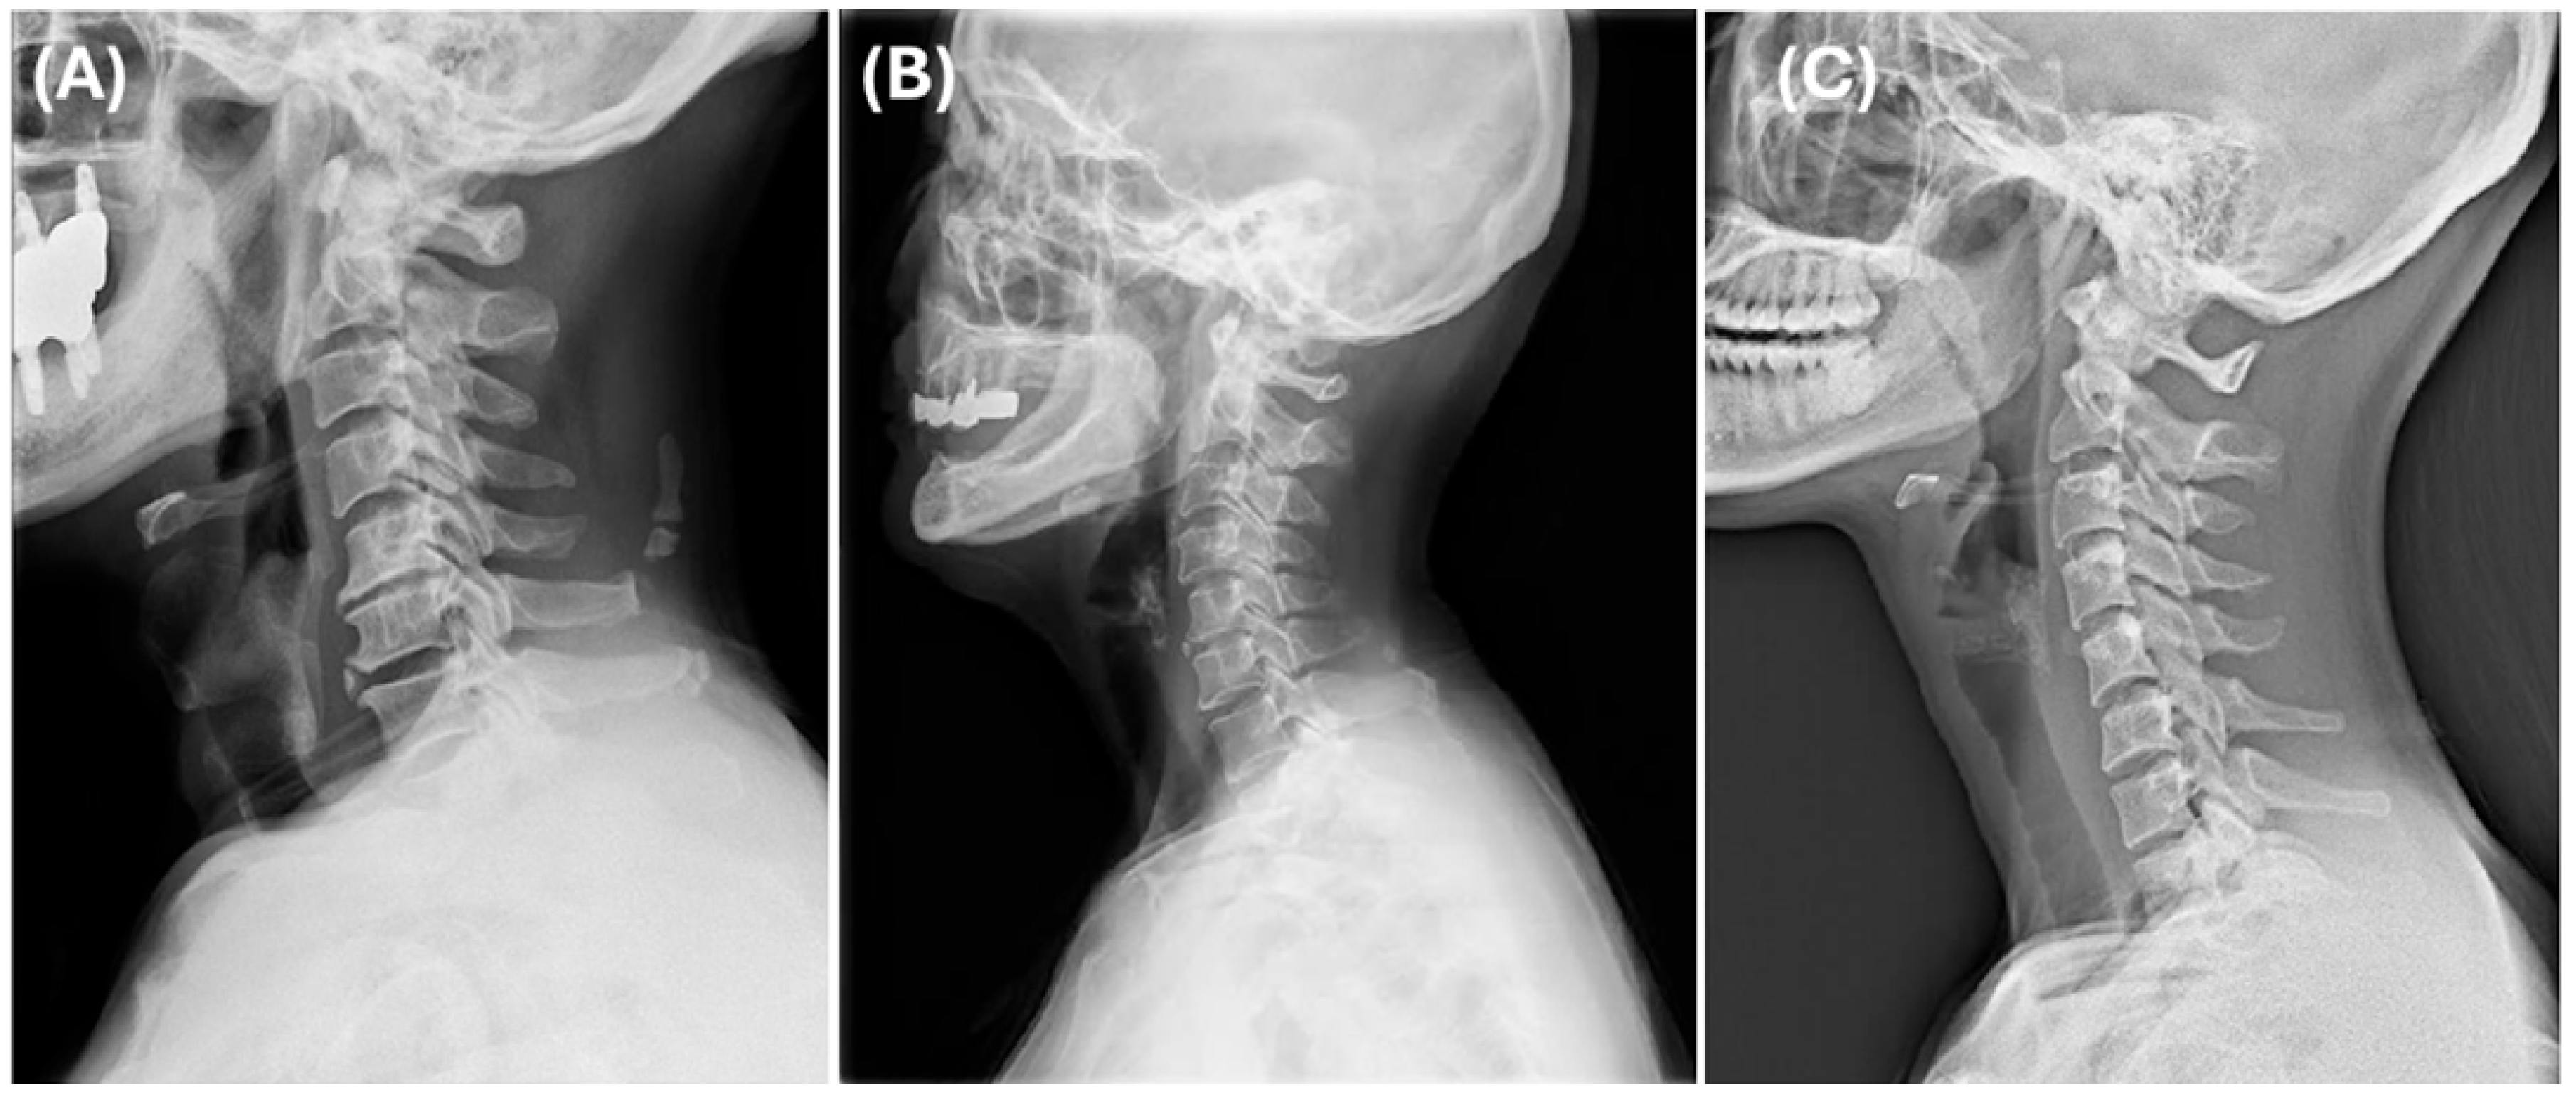

For this study, we included patients with labeled DCM and utilized pre-labeled cervical lateral radiographs (Figure 1). Specifically, annotations included the following: (1) Identification and marking of anatomical landmarks (key points) on the cervical vertebral bodies (C3–C7). (2) Measurement of cervical sagittal parameters such as cervical lordosis, sagittal vertical axis (SVA), vertical length, and curved length. (3) Calculation and labeling of intervertebral angles and vertebral disk heights. (4) Polygon-based segmentation is used to accurately delineate the cervical vertebral region. All eligible lateral cervical radiographs were included in this study. As unsupervised clustering does not require predefined groupings, we used the full dataset to ensure the robustness and generalizability of the clustering results.

Figure 1. Example of labeled lateral cervical spine radiographs used in this study. The dataset includes segmentation and labeling of the vertebral bodies from C3 to C7.